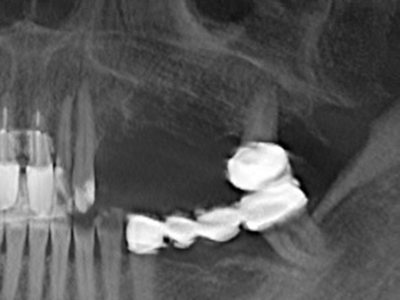

La piezochirurgia presenta altri vantaggi per quanto riguarda la raccolta di blocchi ossei. Oltre all'elevata precisione dell'osteotomia appena descritta, l'utilizzo di puntine per sega molto sottili permette di minimizzare in maniera significativa la perdita di materiale. È molto probabile che si verifichi una maggiore perdita di materiale durante la raccolta utilizzando puntine di strumenti più spessi, in particolare delle frese Lindemann (Lakshmiganthan, Gokulanathan et al. 2012). La separazione basale, necessaria in particolare per i trapianti di blocchi nella zona retromolare, viene semplificata grazie a seghe specificatamente progettate di forma rettangolare; di conseguenza la piezochirurgia è considerata una procedura precisa, semplice e sicura per la raccolta di blocchi di osso nella zona retromolare (Happe 2007) (figg. 1-12).